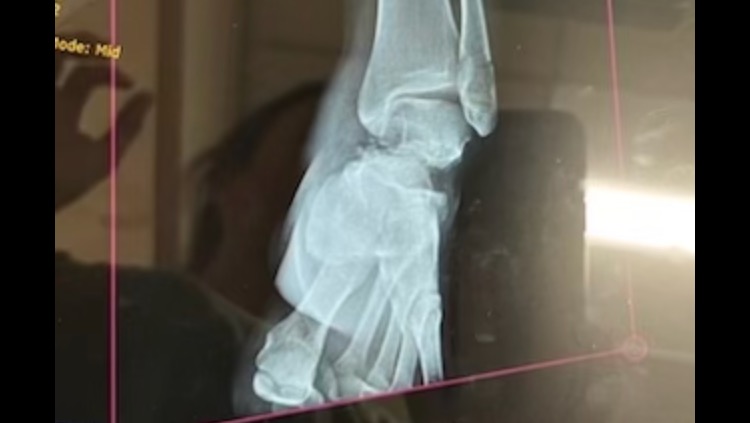

My name is Katherine and I am posting this GoFundMe on behalf of my older sister Mary Rose Cissell. Rose, as I call her, is one of the few people I know who found her true calling in life and has spent the last 15 training and boarding horses as the self-employed business owner of Dark Horse Training Center. One November 21st, 2024, Mary Rose experienced a freak accident while working with a horse when the mare she was riding became spooked and fell in her leg. Though she heard a “crunch” she did not realize the extent of her injury and drive 90 minutes home as her foot swelled and the pain intensified. She was immediately taken to the emergency room and was diagnosed with a broken fibula as well as a compound talus fracture. So essentially her ankle is broken in three different places. She was transferred to the University of Louisville Trauma Center, and the next morning underwent successful surgery to insert a plate and screws to help repair her ankle. Thankfully the surgery went well, and she was sent home to begin recovery after two nights in the hospital. *WARNING* graphic images below.